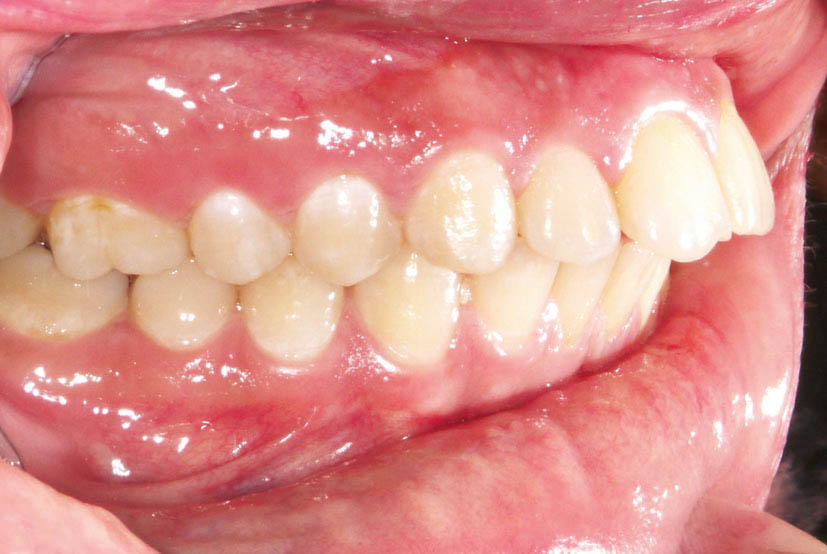

شکل 94-2: اکلوژن یک کاسپ کامل کلاسII در سمت راست

شکل 95-2: اکلوژن نیم کاسپ کلاسII در سمت چپ